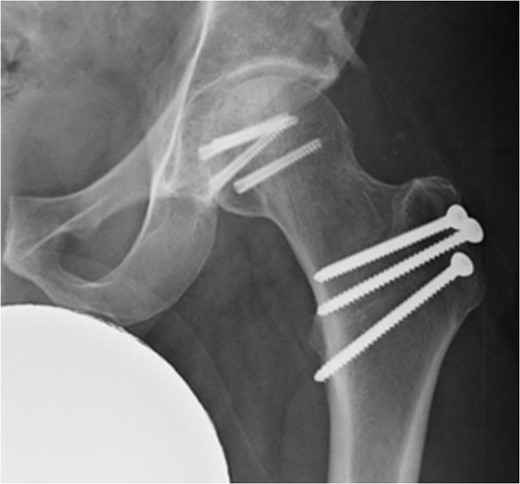

A fit and well man in his 40s had fallen while hiking up a steep hill. He complained of immediate onset, severe left hip pain and inability to move. He was airlifted to our hospital and was found to have shortened externally rotated left leg. Plain X-rays were performed in the emergency department (Fig. 1) identifying isolated fracture–dislocation of the left hip. Computed tomography (CT) was performed while en route to theatre (Figs 2 and 3).

Due to the time involved in the airlift extraction, the hip was dislocated for ~5–6 h. He was attended to by the on-call Consultant Orthopaedic Surgeon, and under general anaesthetic, the hip was reduced with no particular difficulty. The case was referred to the department hip specialist. A further CT scan was performed to assess the position of the fracture to aid in pre-op planning.

At 14 months postoperative, the patient is pleased with his progress. There is no radiographic evidence of avascular necrosis at this stage (Figs 6 and 7). He regularly participates in activities such as cycling, and scores well on the modified Harris Hip Score (81/100), non-arthritic hip score (92.5/100) and SF-12 (41/48).